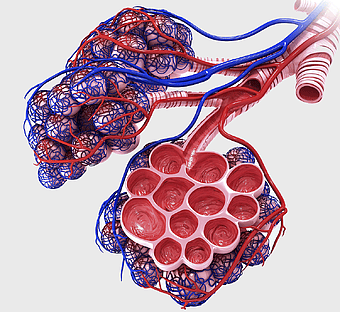

human intestine illustration, Pulmonary alveolus Anatomy, Alveolar venous blood vessels, Bronchiole, respiratory system diagram, pulmonary circulation, lung vascular structure -